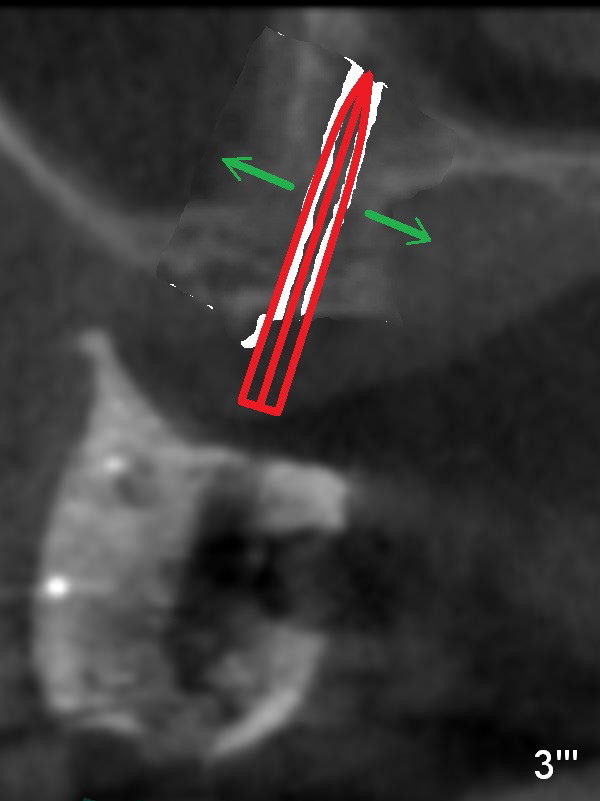

When a large bone expander (Fig.3''' red arrow) is placed, the bone on either sinus or palatal side is displaced (green arrow)